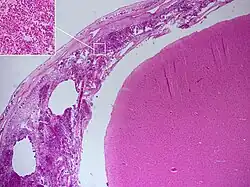

Postmortem

Meningitis can be diagnosed after death has occurred. The findings from a post mortem are usually a widespread inflammation of the pia mater and arachnoid layers of the meninges. Neutrophil granulocytes tend to have migrated to the cerebrospinal fluid and the base of the brain, along with cranial nerves and the spinal cord, may be surrounded with pus – as may the meningeal vessels.[57]